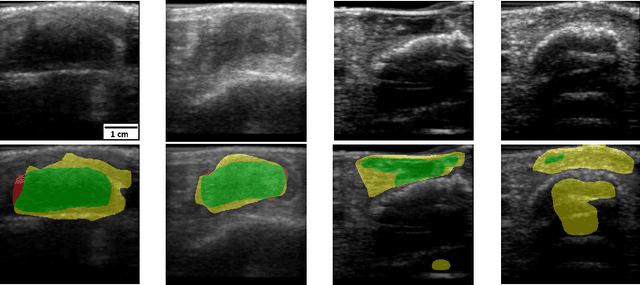

Abstract:Chronic wounds including diabetic and arterial/venous insufficiency injuries have become a major burden for healthcare systems worldwide. Demographic changes suggest that wound care will play an even bigger role in the coming decades. Predicting and monitoring response to therapy in wound care is currently largely based on visual inspection with little information on the underlying tissue. Thus, there is an urgent unmet need for innovative approaches that facilitate personalized diagnostics and treatments at the point-of-care. It has been recently shown that ultrasound imaging can monitor response to therapy in wound care, but this work required onerous manual image annotations. In this study, we present initial results of a deep learning-based automatic segmentation of cross-sectional wound size in ultrasound images and identify requirements and challenges for future research on this application. Evaluation of the segmentation results underscores the potential of the proposed deep learning approach to complement non-invasive imaging with Dice scores of 0.34 (U-Net, FCN) and 0.27 (ResNet-U-Net) but also highlights the need for improving robustness further. We conclude that deep learning-supported analysis of non-invasive ultrasound images is a promising area of research to automatically extract cross-sectional wound size and depth information with potential value in monitoring response to therapy.